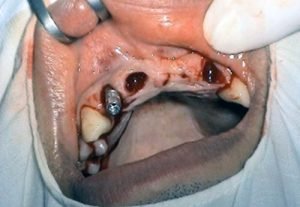

Prosthetic treatment in a toothless jawbone carried - 4 implants

Implantation solution of the posterior toothless sections in the jaw

Solution of frontal defect in the jaw

Solution of frontal defect in the jaw in a jaw orthopedic anomaly

Implantation solution of complete toothlessness in the jaw